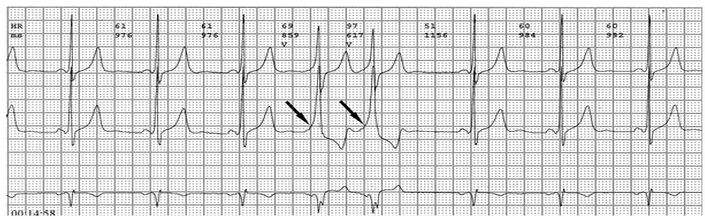

心电图检查及其特征

各旁路引起预激的心电图特征如下:

1、房室旁道

(1)PR间期(实质上是P-δ间期)缩短至0.12秒以下,大多为0.10秒;

(2)QRS时限延长达0.11秒以上;

(3)QRS波群起始部粗钝,与其余部分形成顿挫,即所谓预激;

(4)继发性ST-T波改变。

上述心电图改变尚有分为A、B两型的。A型的预激波和QRS波群在V1导联均向上,而B型V1导联的预激波和QRS波群的主波则均向下;前者提示左室或右室后底部心肌预激,而后者提示右室前侧壁心肌预肌。这种分类方法虽然受到预激是不同部位旁路所致的多变QRS波群的限制,但有助于区别旁路的心室端在左或右、前或后,因而沿用至今。

PR间期正常,QRS波群增宽,有预激波。预激综合征室上性心动过速发作时,预激表现大多消失,心电图表现为QRS波群形态正常的室上性心动过速。并发房扑或房颤时,QRS保持预激特征的不少见,心电图表现为QRS波群畸形宽大的房扑或房颤;心室率大多超过200次/分,甚至可达300次/分。房扑时可呈1:1房室传导,并可能辨认房扑波。房颤时心室律不规则,长间歇之后可见到个别QRS波群形态正常(可能为旁路不应期延长,房室结内隐匿传导作用消失后,冲动全部或大部经房室结传导所致),并可能辨认房颤波。心室率极快时,还可伴有频率依赖性心室内传导改变。